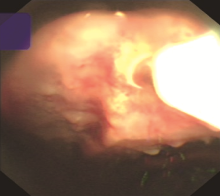

Objective: To evaluate the diagnostic value of cryobiopsy in patients with suspected tuberculous pleurisy by comparing cryobiopsy and biopsy forceps biopsy. Methods: A prospective study was conducted. A total of 73 patients with suspected tuberculous pleurisy were consecutively included in Harbin Chest Hospital from May 2022 to August 2024 in accordance with the enrollment criteria. All enrolled patients underwent internal medicine thoracoscopic biopsy forceps biopsy and cryobiopsy simultaneously. Both the biopsy tissue and pleural effusion were tested by GeneXpert MTB/RIF, Mycobacterium tuberculosis resistance gene-on-chip method (referred to as “drug resistance gene-on-chip method”), and Mycobacterium tuberculosis BACTEC MGIT 960 (referred to as “MGIT 960”) culture and pathological examination. Based on the final clinical diagnosis results, the differences in tissue specimen diameter, pathological positive rate, etiological positive rate, complications and other indicators of biopsy forceps biopsy and cryobiopsy were compared, and the diagnostic value of internal thoracoscopic cryobiopsy for patients with suspected tuberculous pleurisy was evaluated. Results: All 73 patients obtained a definitive diagnosis. Among them, 64 patients (87.7%, 64/73) achieved a definitive diagnosis by biopsy forceps biopsy, while 71 patients (97.3%, 71/73) did so by cryobiopsy. A total of 60 cases (82.2%, 60/73) were diagnosed with tuberculous pleurisy, including 43 cases (58.9%, 43/73) of drug sensitive tuberculous pleurisy and 17 cases (23.3%, 17/73) of drug-resistant tuberculous pleurisy (including 3 cases of monodrug-resistant, 8 cases of multidrug-resistant, 1 case of polydrug-resistant, 2 cases of pre-extensively drug-resistant, and 3 cases of extensively drug-resistant). The remaining 13 cases (17.8%, 13/73) were diagnosed with pleural effusion due to other causes, including 6 cases (8.2%, 6/73) of malignant pleural mesothelioma, 2 cases (2.7%, 2/73) of adenocarcinoma, 1 case (1.4%, 1/73) of squamous cell carcinoma, 1 case (1.4%, 1/73) of small cell neuroendocrine carcinoma, 2 cases (2.7%, 2/73) of inflammation, and 1 case (1.4%, 1/73) of amyloidosis. The diameter of the tissue specimen of cryobiopsy ((7.47±0.71) mm) was significantly larger than that of biopsy forceps biopsy ((2.34±0.22) mm), and the histopathological positivity rate of cryobiopsy (97.3%, 71/73) was significantly higher than that of biopsy forceps biopsy (87.7%, 64/73); the differences were statistically significant (t=58.820, P<0.001; χ2=4.818, P=0.028). The histopathogenic positivity rate of cryobiopsy (GeneXpert MTB/RIF: 91.7%, 55/60; resistance gene chip examination: 61.7%, 37/60; MGIT 960 culture: 73.3%, 44/60) was significantly higher than those of biopsy clamp biopsy (GeneXpert MTB/RIF was 70.0% (42/60), drug resistance gene microarray was 28.3% (17/60), MGIT 960 culture was 40.0% (24/60)), and the differences were statistically significant (χ2=8.015, P=0.005; χ2=13.470, P<0.001; χ2=13.570, P<0.001). The diagnostic sensitivity of cryobiopsy for tuberculosis pleurisy (98.5%, 66/67) was significantly higher than that of biopsy forceps biopsy (88.9%, 56/63), and the difference was statistically significant (χ2=5.202, P=0.023). No serious adverse reactions occurred postoperatively in either biopsy methods. A total of 16 cases (21.9%, 16/73) developed mild chest pain, among which the incidence of chest pain in cryobiopsy (5.5% (4/73)) was lower than that in biopsy (16.4%, 12/73), and the difference was statistically significant (χ2=4.492, P=0.034). Conclusion: Internal thoracoscopic cryobiopsy has high diagnostic sensitivity and the advantage of high safety for patients with suspected tuberculous pleurisy, and can further improve the precise treatment level of tuberculous pleurisy through drug susceptibility testing.